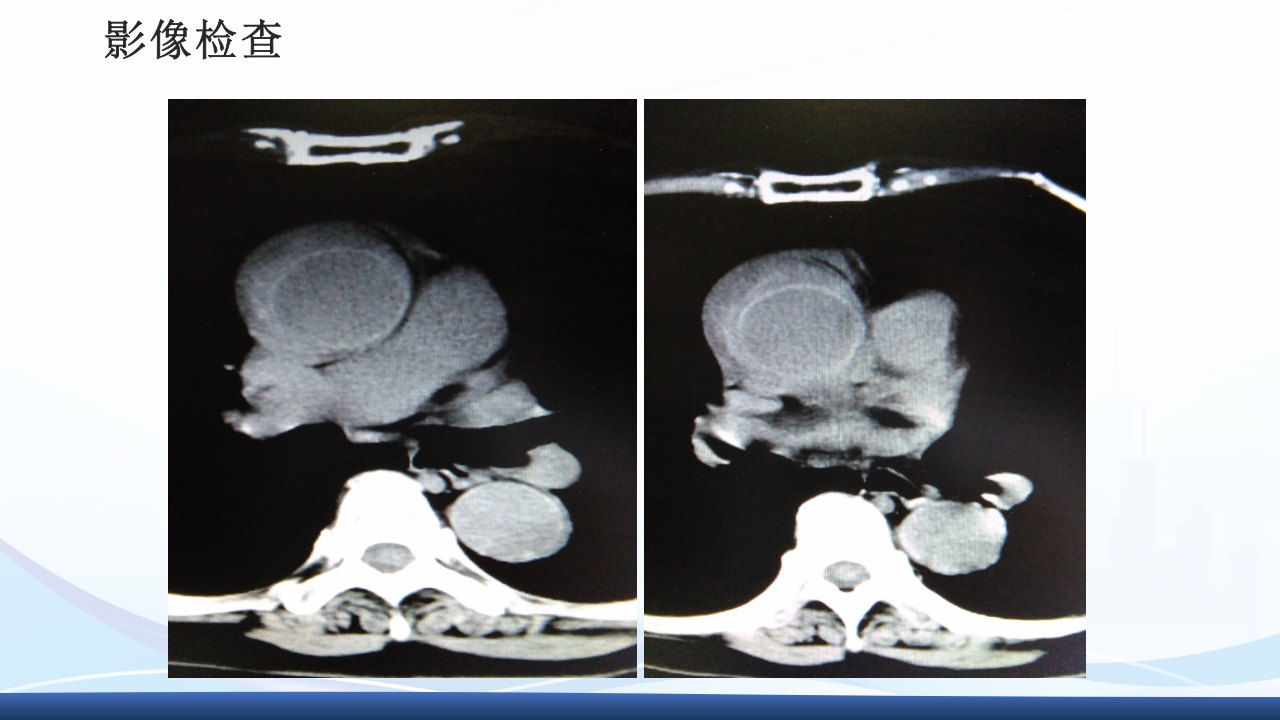

大纲 1 主动脉夹层的概念 2 病因与发病机制、分型 3 临床表现3 、辅助检查 4 主动脉夹层的诊断、治疗 5 病例介绍 64 护理诊断与措施、健康宣教 解剖图 解剖图 主动脉夹层的概述 主动脉夹层(aortic dissection AD)指主动脉壁中层 撕裂、分离,使主动脉壁内形成血肿,并沿纵向延伸。 AD最常发生在50-70岁的男性,男女性别比约2-5:1, 是与人类主动脉有关的最常见的死亡原因。 Thoraci caorta Abdomin alaorta Aortic dissection Aorta Blood in wall of artery Blood in artery 病因 结缔组织遗传缺陷性疾病:如马方(Marfan)综合征、埃-当(Ehlers-Danlos)综 合征、先天性主动脉缩窄、二叶主动脉瓣及二尖瓣脱垂等患者。 高血压:临床与动物实验发现,不是血压的高度...